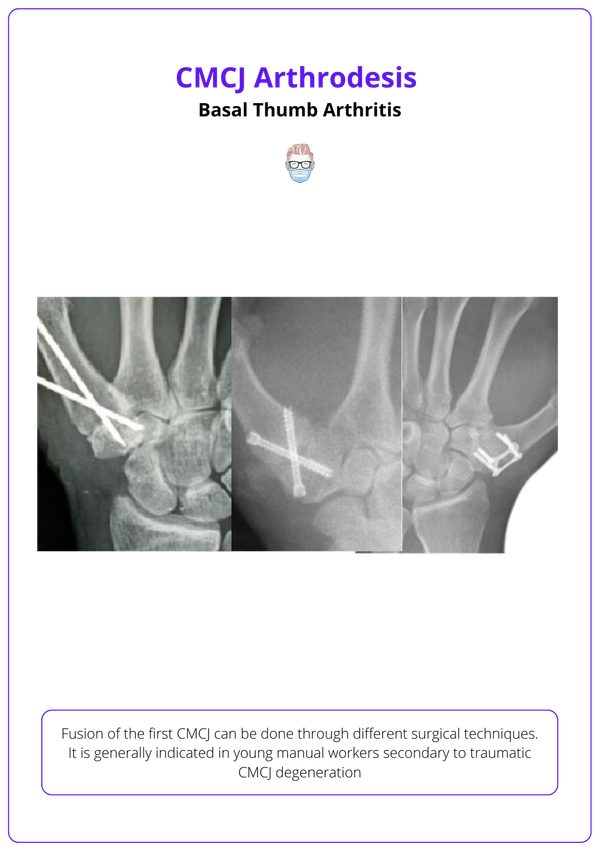

From www.theplasticsfella.com